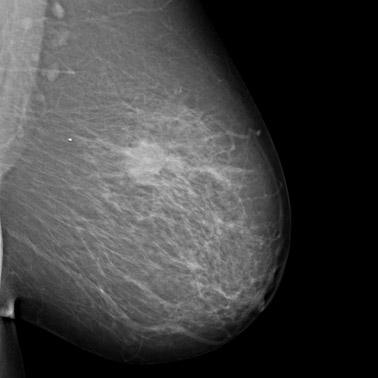

MRT zur Diagnostik der weiblichen Brust (Mammadiagnostik, Mamma-MRT)

• Brust

Eine Kernspintomographie der Brust wird eingesetzt, wenn die Tastuntersuchung, Mammographie, Sonographie oder eine Biopsie keinen eindeutigen Befund ergeben haben und man mit Hilfe einer weitere Untersuchung Brustkrebs auszuschließen will.

Kernspintomographie (MRT, Magnetresonanztomographie): Die Mamma-MRT, ein Untersuchungsverfahren, das im Gegensatz zur Röntgentechnik mit Magnetfeldern arbeitet, findet bei uns in der Brustkrebsdiagnostik ebenfalls Anwendung. Es ist in der Regel dann erforderlich, wenn die vorhergehende Untersuchung per Mammographie oder Sonographie keinen klaren Befund ergeben hat.

Brusttumor 1

Brusttumor 2